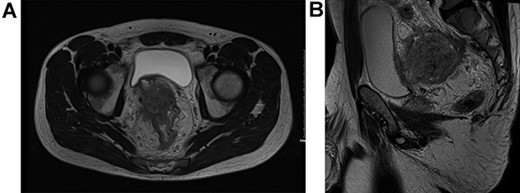

The patient underwent a defunctioning ileostomy at diagnosis. He completed 6 cycles of modified chemotherapy regime `FOLFIRINOX' (Folinic acid, fluorouracil, irinotecan and oaxliplatin) tolerated reasonably well, ECOG 0-1. He received Neulasta injections to prevent neutropenia during chemotherapy. This was followed by long course chemoradiotherapy (Capecitabine 825 mg/mtr2 twice daily, 5 days per week during radiotherapy). Repeat imaging 6 weeks post TNT demonstrated excellent response, reduction in bulky tumor previously noted on peritoneal reflection and bladder and extensive low signal scarring between rectum, peritoneal reflection, bladder and right sided internal iliac vessels (Fig. 2).

Post total neoadjuvant therapy (A) axial view and (B) sagittal view.